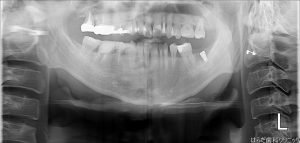

最後にレントゲン写真で確認をします。

しっかりと埋入されていますね(^^♪